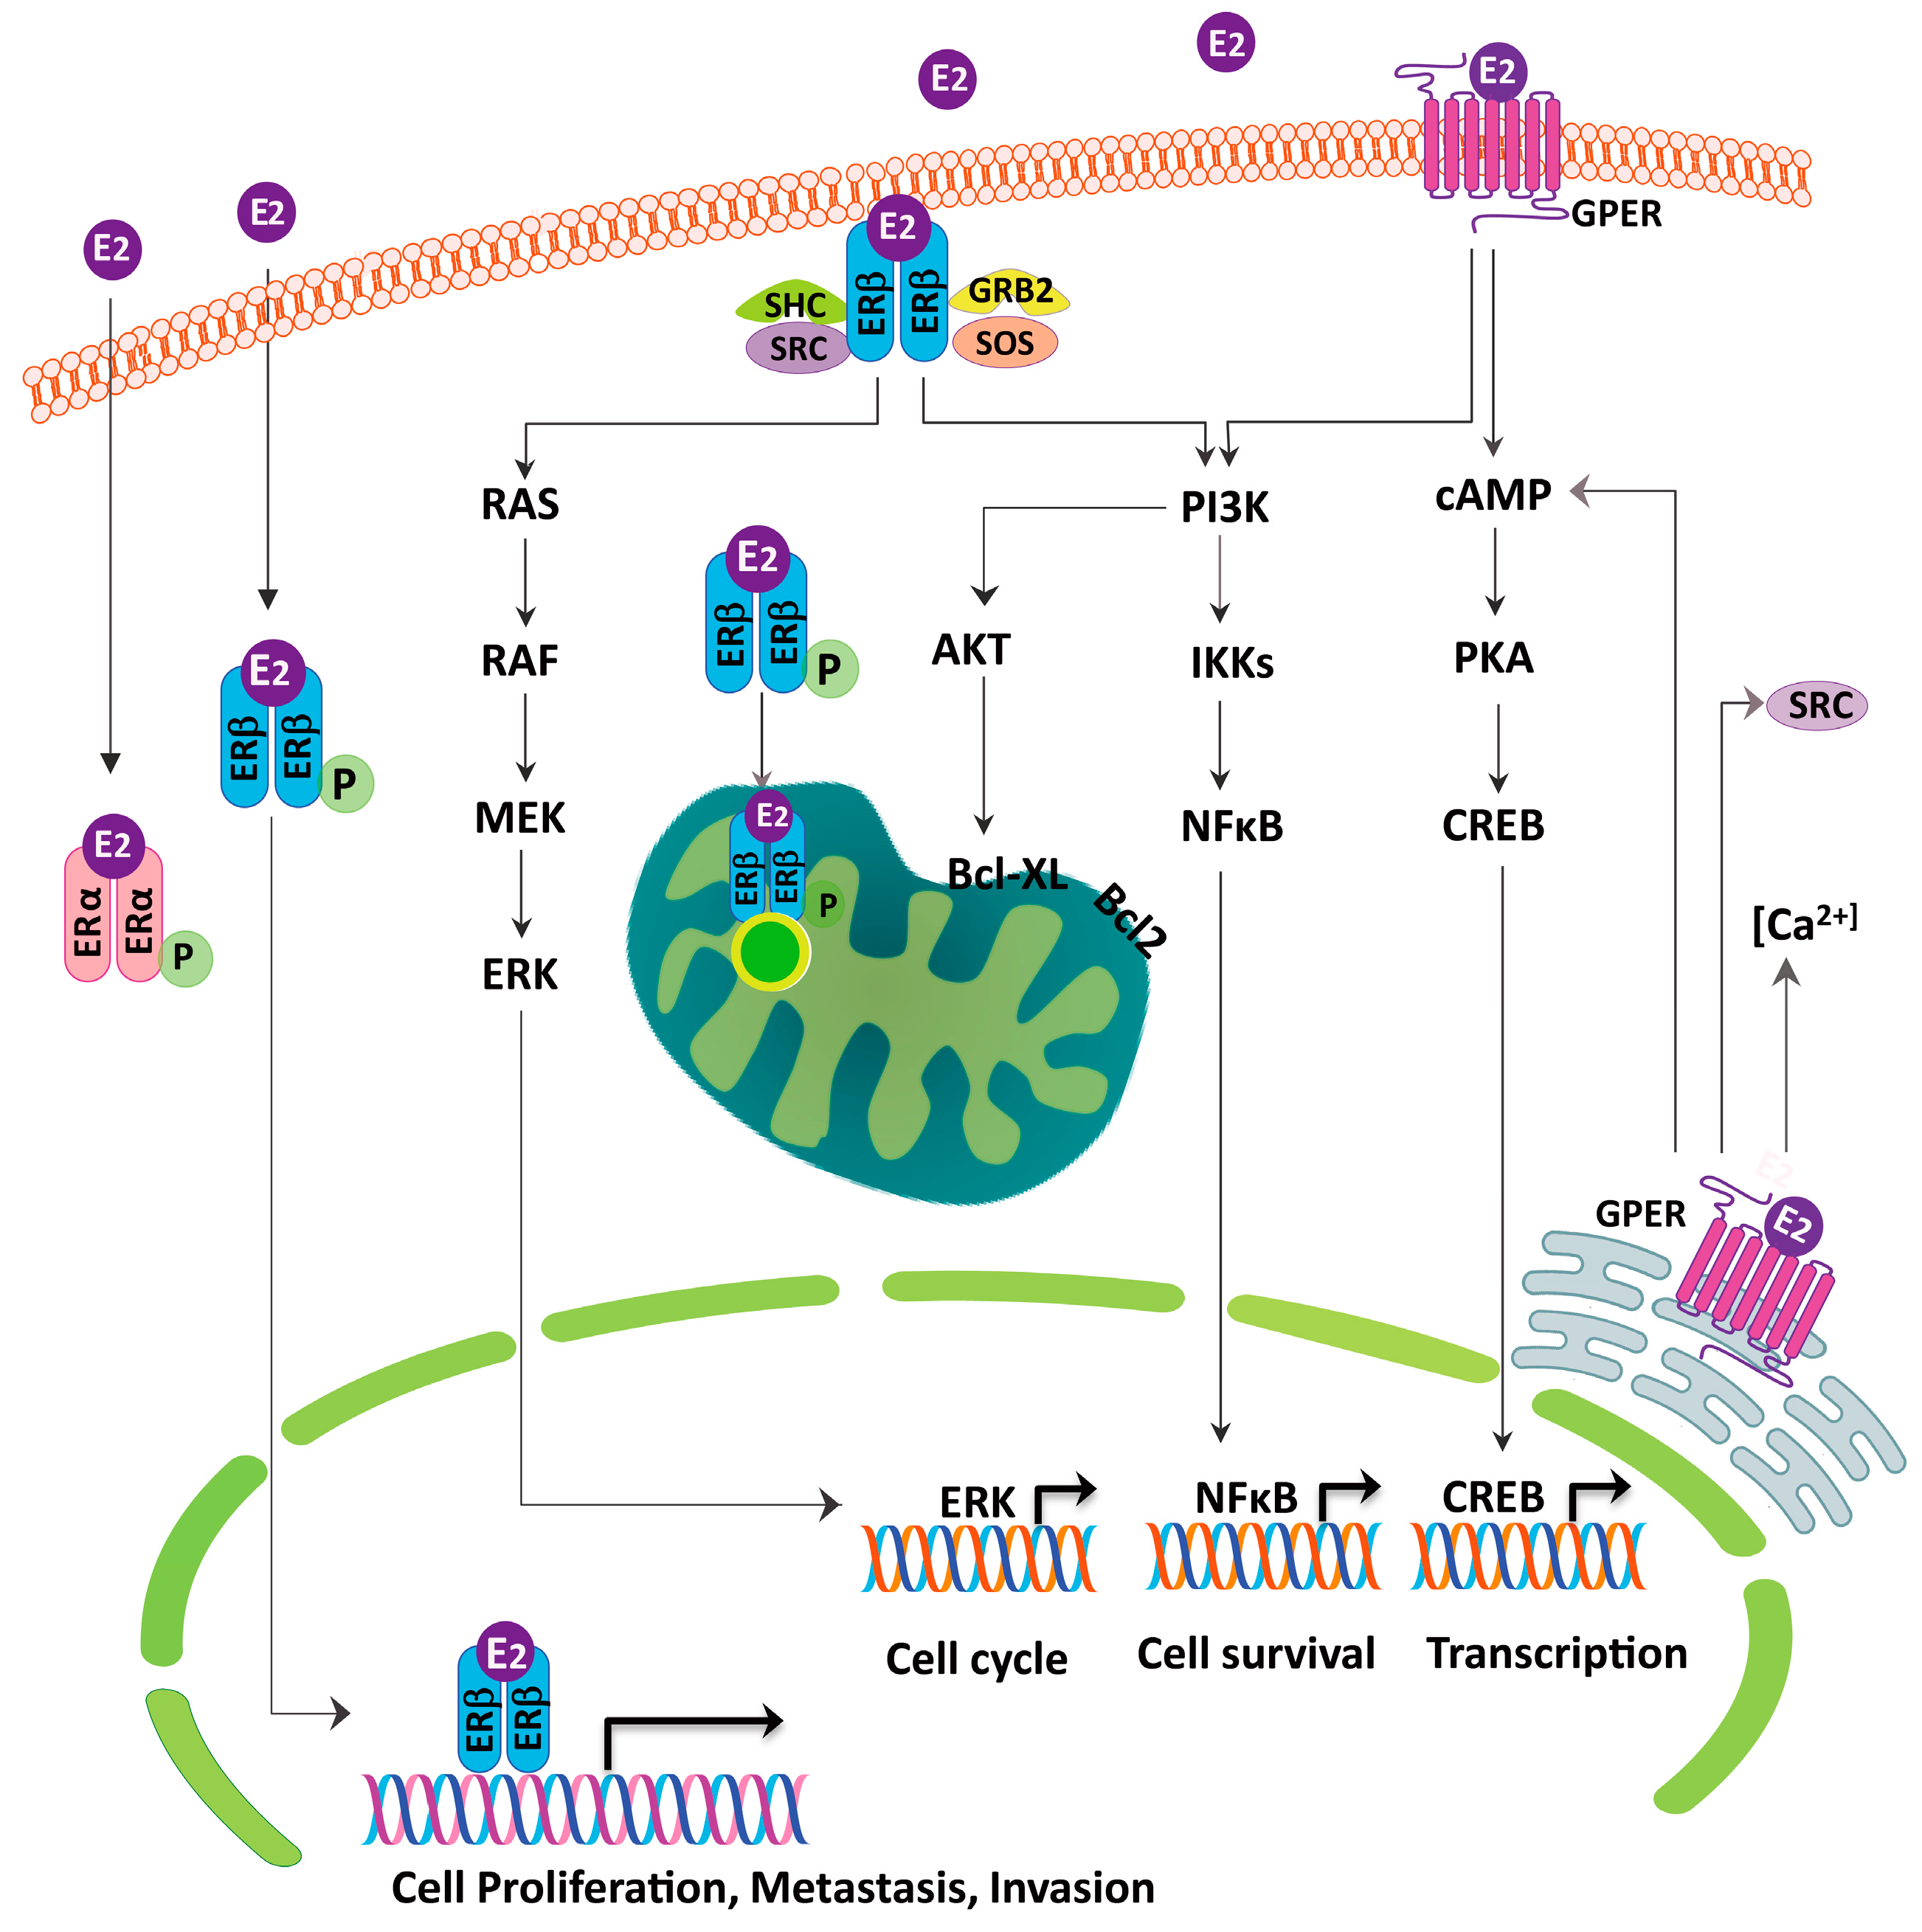

2. Estrogen Receptor in Lung Cancer

4. ER as Targets for Lung Cancer Therapy and Relationship with EGFR